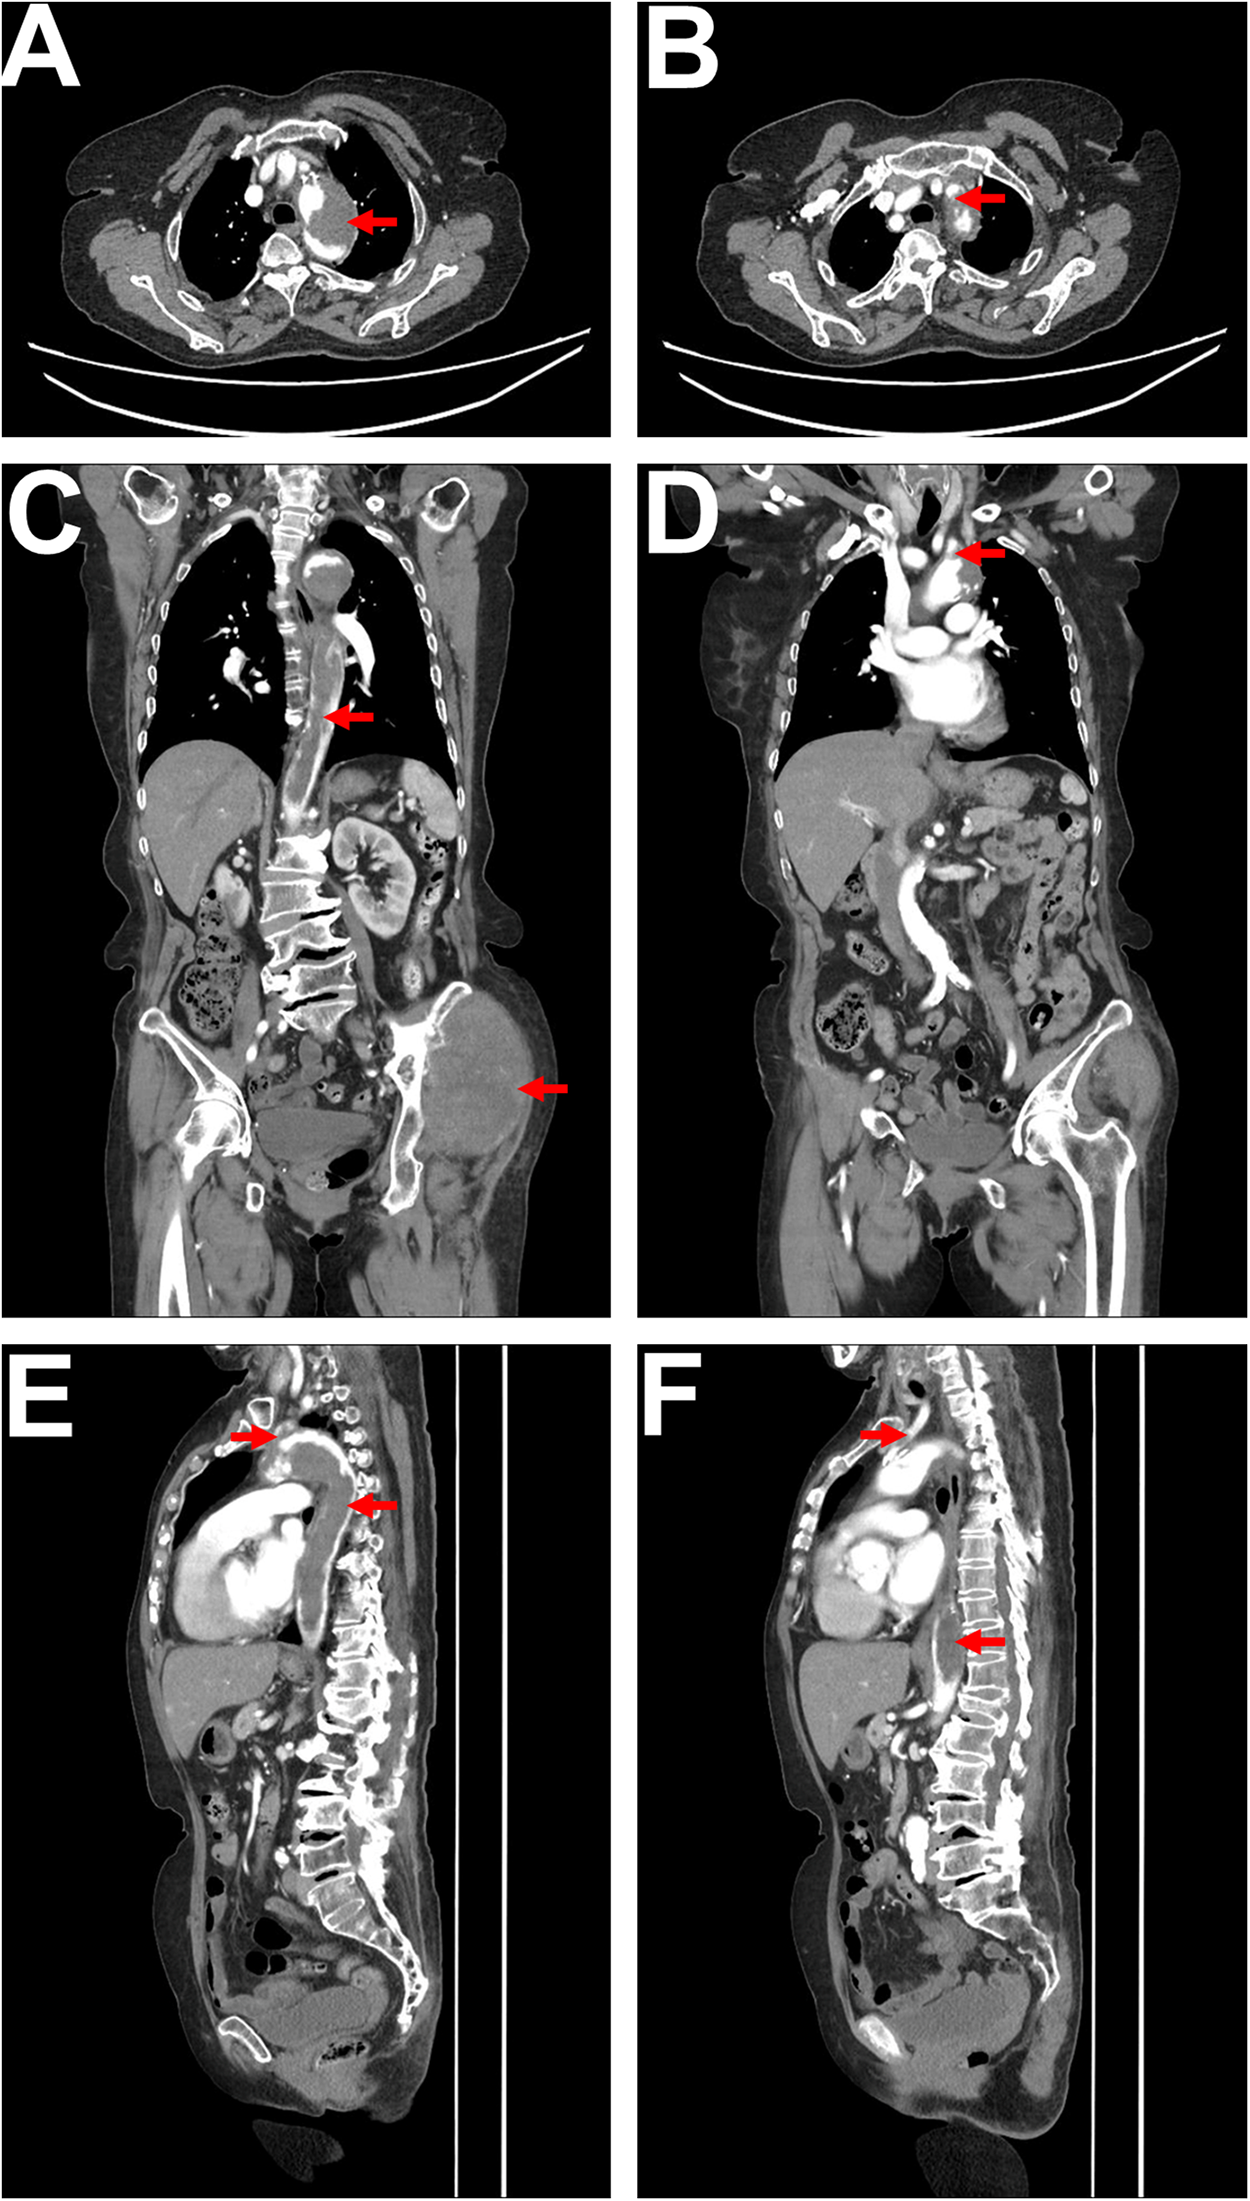

To further clarify the aortic lesion, an aortic CTA was performed, which showed irregular filling defects in the aortic arch and descending aorta. The left subclavian artery origin and the left common carotid artery origin were also affected, with a high likelihood of tumor involvement based on the patient's medical history (Figures 2A–F). The CTA also revealed atherosclerotic changes in the aorta and its branches. Lower limb arterial ultrasound indicated bilateral iliac artery sclerosis, with arterial sclerosis and multiple plaque formations in both lower limbs. Cardiac ultrasound detected a hyperechoic mass within the descending aorta, measuring approximately 31 × 25 mm, with a relatively clear boundary, irregular shape, minimal movement, and localized lumen narrowing.

Figure 2

CTA imaging. (A) Axial CTA shows a low-density filling defect within the aortic arch, with no significant enhancement, irregular margins, and a lobulated appearance, resulting in significant lumen narrowing, as indicated by the red arrow. (B) Axial CTA reveals a low-density filling defect at the origin of the left subclavian artery, connected to the lesion within the aortic arch, with lumen narrowing, as indicated by the red arrow. (C) Coronal CTA displays a long low-density filling defect within the aorta (extending from the superior margin of the aortic arch to the level of the left renal upper pole), characterized by irregular margins and nearly complete occlusion of the lumen, as indicated by the red arrow. The soft tissue mass in the left hip is also visible, as indicated by the red arrow. (D) Coronal CTA shows a low-density filling defect at the origin of the left subclavian artery, connected to the lesion in the aortic arch, as indicated by the red arrow. (E) Sagittal CTA illustrates a long low-density filling defect within the aorta (from the superior margin of the aortic arch to the level of the left renal upper pole), with irregular margins (indicated by the red arrow), alongside a low-density filling defect at the origin of the left subclavian artery connected to the lesion in the aortic arch, as indicated by the red arrow. (F) Sagittal CTA shows a low-density filling defect within the left common carotid artery (indicated by the red arrow), as well as low-density lesions in the descending thoracic aorta and abdominal aorta (indicated by the red arrow).

Imaging studies used for evaluation include CT angiography (CTA), magnetic resonance angiography (MRA), and 18-fluorodeoxyglucose positron emission tomography (18F-FDG PET/CT) (4, 5). The CT characteristics of aortic sarcoma include prominent intraluminal growth, irregular surface margins, lobulated or mildly lobulated appearance, minimal or absent contrast enhancement, thickening and/or enhancement of the aortic wall, extravascular extension, and lymph node or distant metastasis (4, 5, 7). The patient we reported had intimal angiosarcoma affecting the aortic arch, descending thoracic aorta, and abdominal aorta, with CT showing prominent intraluminal growth, irregular surface margins, slight lobulation, and minimal contrast enhancement, along with soft tissue metastasis in the hip, consistent with findings reported in the literature (4, 5, 7). Contrast-enhanced and perfusion MRI can suggest tumor formation (7). MRI has been shown to be superior to CT in differentiating tumors from the vascular wall and surrounding soft tissues (9). Previous literature reports that almost all aortic sarcomas exhibit metabolic activity on 18F-FDG PET, which can better differentiate them from metabolically inactive atherosclerosis, intraluminal thrombus, and chronic aortic dissection (13).

In this case, the angiosarcoma affected the aortic arch, descending thoracic aorta, abdominal aorta, as well as the left common carotid artery and left subclavian artery arising from the aortic arch. The aortic CTA showed intimal lesions with significant intraluminal growth and irregular surface margins. The patient experienced lower limb arterial embolism and developed paraplegia, with the injured spinal cord segment being the T10 thoracic segment.